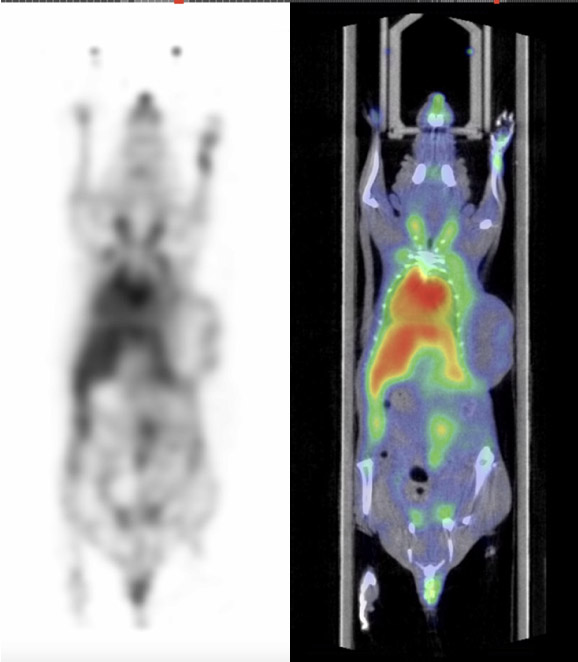

CASE 4: Rat PET/CT imaging with 18F-FDG

workimg

• Courtesy of: D.Panetta and P.A. Salvadori, IFC-CNR Pisa, Italy

Research objective:Rat PET/CT imaging with F18-FDG for accessing brain and heart uptake

Animal model:Wistar rat, 294g

Acquisition protocol:PET: 15 min acquisition time, 1 bed position; CT: 20 s acquisition time, 1 bed position, 80 kVp, 1 mA

Processing and reconstruction protocol:PET: 3D-OSEM, 0.42 x 0.42 x 0.855 mm voxel size; CT: 0.08 mm isotropic voxel size

Biomarker or contrast agent:18F-FDG, activity: 200 uCi, volume: 0.3 mL, imaging at 60 min post injection